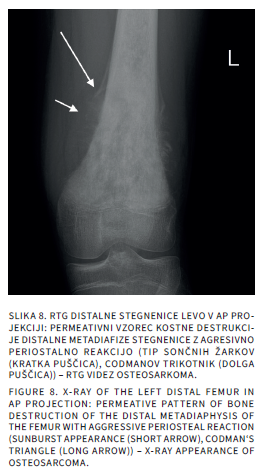

Bolečine v mišičnoskeletnem sistemu so v otroškem obdobju sorazmerno pogoste. Delimo jih na akutne in kronične, slednje trajajo več kot 3 mesece. Diferencialna diagnoza tako akutnih kot kroničnih bolečin v sklepih pri otrocih je široka. Slikovne preiskave so poleg anamneze, klinične slike in laboratorijskih izvidov pomembne v diagnostičnem postopku iskanja vzrokov bolečine. Katero slikovno metodo uporabimo najprej, je odvisno od mesta bolečine in od prizadetosti tkiva. Pri mehkotkivnih spremembah in oteklinah sklepov je prva diagnostična metoda ultrazvočna preiskava, pri sumu na prizadetost kosti pa rentgensko slikanje. Če je potrebno, sledi magnetnoresonančno slikanje ali računalniška tomografija. V prispevku bomo opisali anatomske in morfološke značilnosti otroškega skeleta, ki lahko dajejo videz patoloških sprememb ter slikovne diagnostične postopke pri akutnih in kroničnih bolečinah v sklepih.